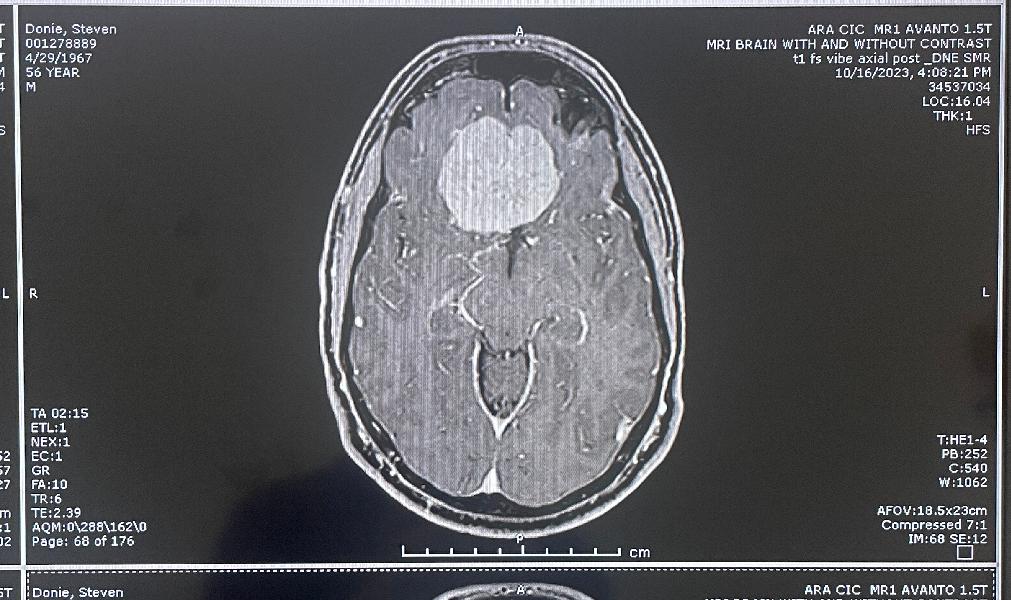

MRI, front and side views

Another clear top view

more MRI